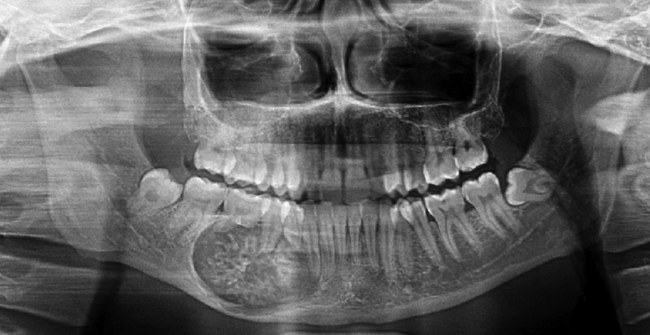

florid cemento-osseous dysplasia